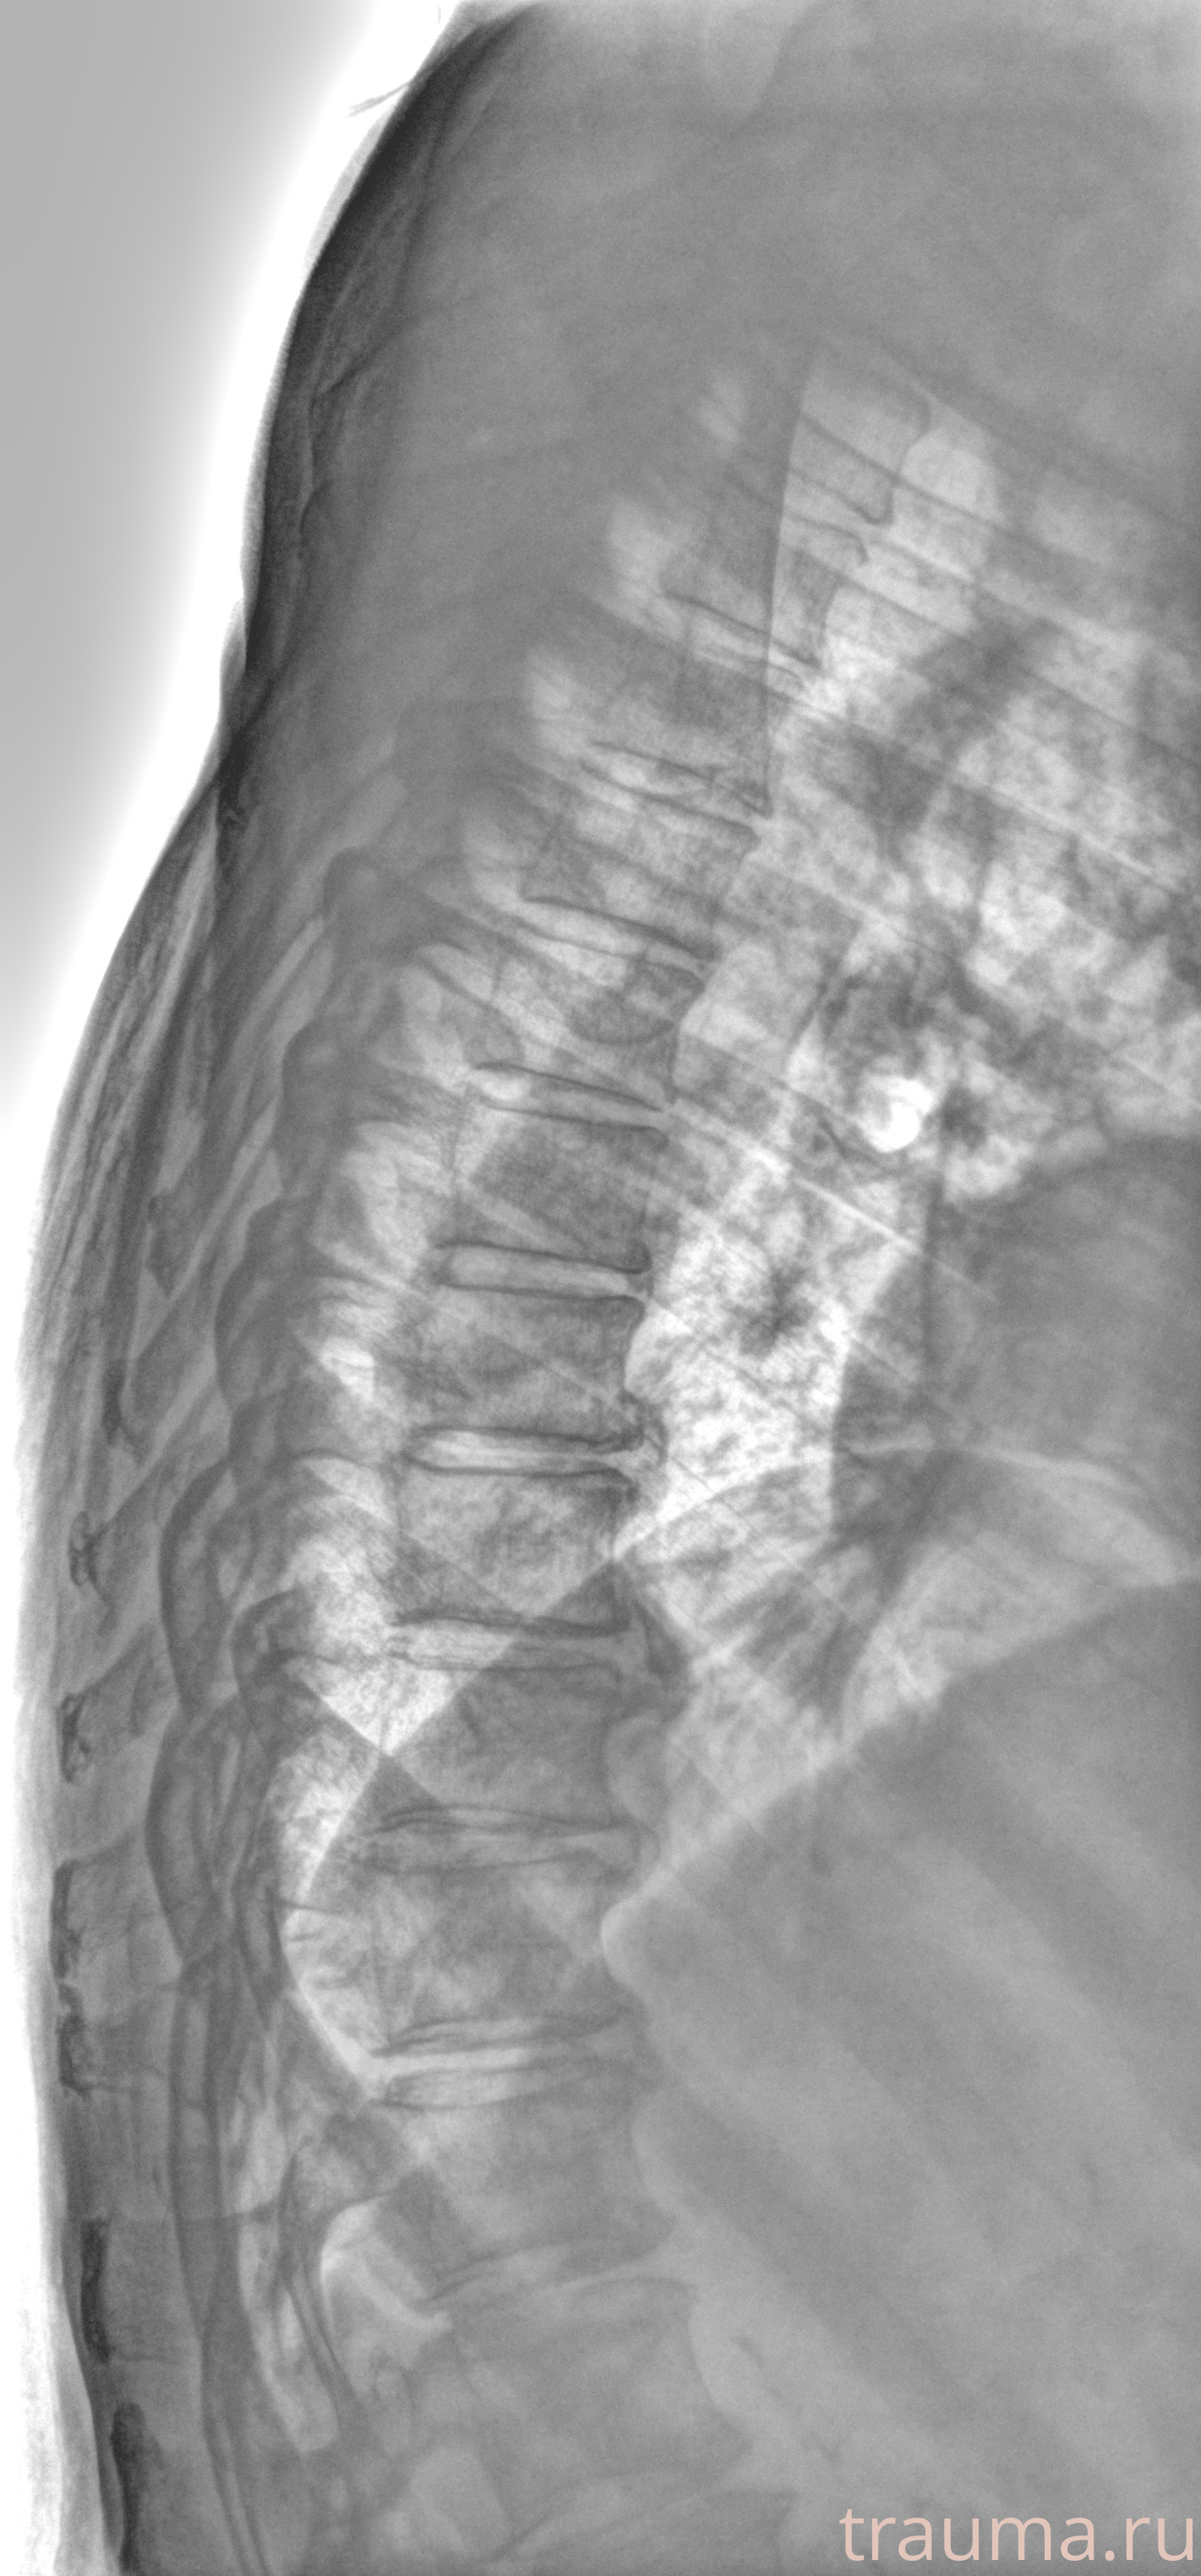

Рентген на дому: по вашему адресу приезжает врач-рентгенолог, травматолог-ортопед с мобильным рентгеновским аппаратом, проводит диагностику травмы или заболевания, делает необходимые рентгенограммы, дает рекомендации по дальнейшему лечению. Получить качественные снимки в домашних условиях возможно благодаря уникальной методике, разработанной МосРентген Центром для института  Склифосовского